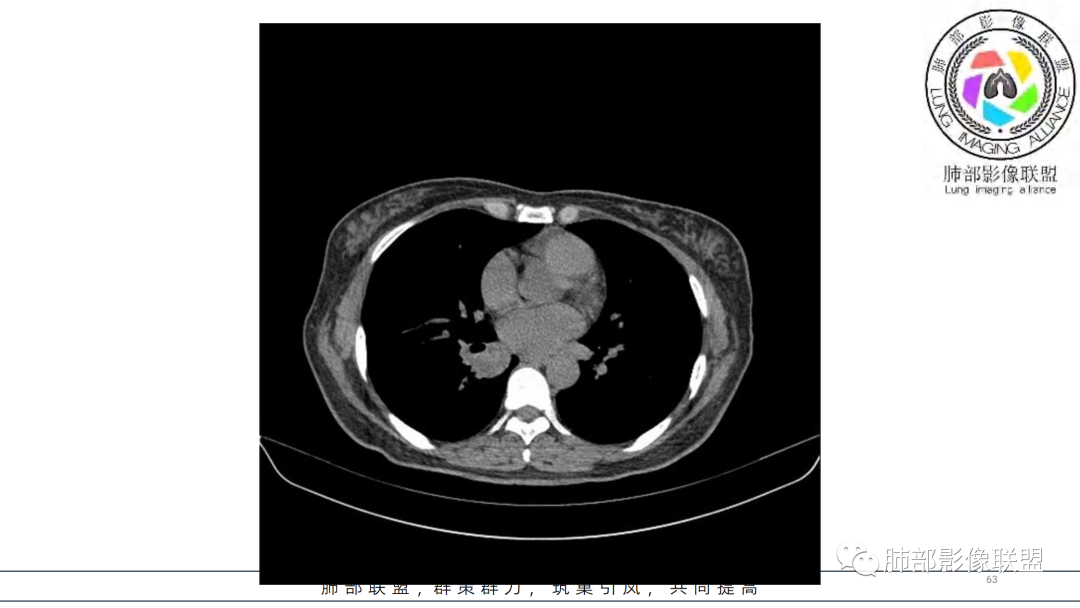

2.右肺下叶及中间段支气管后方类圆形块影,边界较清楚,未见分叶及毛刺,病灶部分突入支气管腔内(冰山一角),局部管腔狭窄,相应肺叶未见片影或体积变化。

3.块影密度均匀,未见液化坏死及钙化,渐进性强化,强化显著。

4.双肺门及纵隔未见增大淋巴结。未见胸腔积液。

中青年女性,支气管管腔内外肿块(“冰山征”),边界较清楚,强化显著,未见阻塞性肺不张,尽管未出现“类癌综合征”临床表现,仍然符合典型类癌影像学表现。